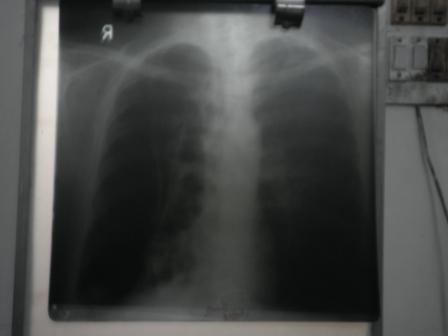

bunty pleural effusion case from mathura

bunty xray after treatment in 15 days

bunty xray before treatemtn